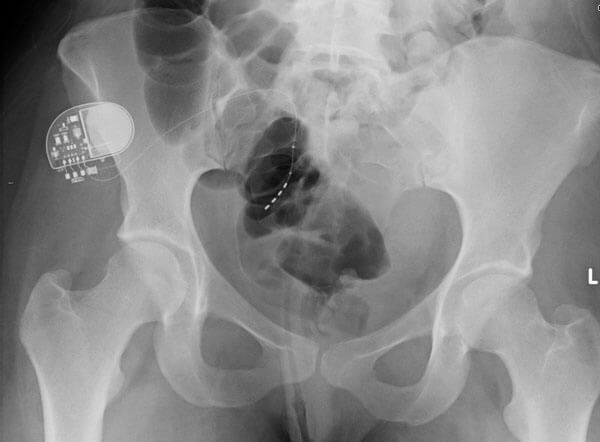

Reproduced with permission of Medtronic, Inc.

Image provided courtesy of Prof Hashim Hashim, Bristol Urological Institute.

- What is the device seen in the picture and the x-ray below?

- The Medtronic sacral nerve stimulator, sacral neuromodulation device, implantable pulse generator (IPG). Sacral nerve stimulation is also known as InterStim® Therapy.

- Overactive bladder, non-obstructive urinary retention and faecal incontinence

- Infection, pain at the implant site, leg pain, bowel disturbance, device explantation, lead migration, seroma, and haematoma. Battery depletion requiring replacement (usually between three to seven years depending on device settings), lack of efficacy and secondary loss of efficacy are other problems encountered.

- The first stage of SNS is an evaluation phase or test phase. The patient undergoes insertion of a temporary electrode with a unipolar electrode under local or general anaesthetic alongside a sacral nerve (generally S3) and connected to an extension lead to an external neurostimulator. Alternatively, a permanent tined lead can be inserted in the same position and tunnelled to the potential battery site, then connected via an extension lead to the external stimulator. The patient is then evaluated for two to four weeks with adjustments to the level of stimulation if required using a bladder diary. If the treatment is successful, the patient proceeds to implantation of a permanent IPG. If unsuccessful the wire is simply removed.

- Around 70% success [1].